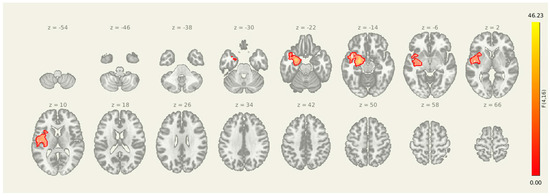

3.2. Pre Amygdala Seed

Prior to intervention, seed-to-voxel analysis from the amygdala revealed widespread connectivity with multiple cortical and subcortical regions (Figure 1). Significant clusters were observed in bilateral sensorimotor and frontal areas, including the left parahippocampal gyrus (MNI: −36, +06, −28; cluster size = 1396 voxels; p-FDR < 0.001), right superior parietal lobule (+38, −56, +60; 575 voxels; p-FDR < 0.001), right insular cortex (+46, −06, +16; 406 voxels; p-FDR < 0.001), and right thalamus (+18, +10, −16; 383 voxels; p-FDR < 0.001). Additional clusters were detected in the left superior parietal lobule, right cerebellum, and prefrontal cortex, further supporting elevated amygdala connectivity within regions implicated in sensory integration, emotional processing, and motor readiness (Figure 2).

Figure 1.

Pre-intervention amygdala connectivity map. A 3D surface rendering illustrates widespread resting-state functional connectivity from the amygdala seed at baseline. Significant clusters were observed in bilateral cortical and subcortical regions, including the left parahippocampal gyrus, right superior parietal lobule, right insular cortex, and right thalamus (all p-FDR < 0.001).

Figure 2.

Multi-slice view of amygdala seed connectivity at pre-intervention. Displayed clusters correspond to those reported in Table 2, showing significant resting-state connectivity between the amygdala and bilateral cortical regions, including sensorimotor and prefrontal cortices. All results are thresholded at p-FDR < 0.05 and shown in MNI space.